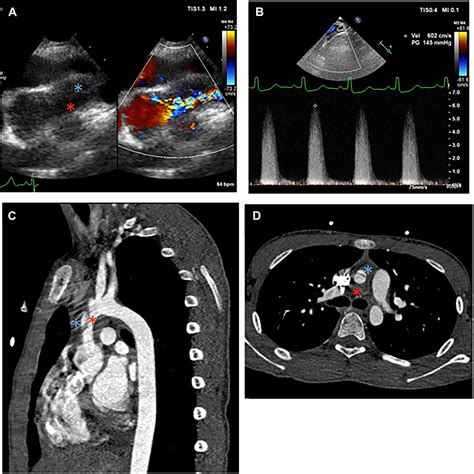

• Echocardiogram: This is a non-invasive ultrasound test that provides detailed images of the heart and aorta. It can help identify the location and severity of the narrowing.

• Magnetic Resonance Imaging (MRI) or Computed Tomography (CT) Scan: These imaging techniques can provide detailed images of the heart and aorta, helping to assess the extent of the narrowing and plan treatment.